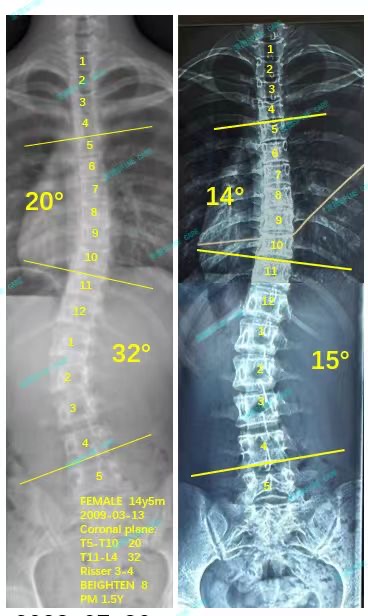

来到衷德不知不觉两年多了,我和妈妈都十分信赖杨博士和所有康复师,最近脱支后拍x片显示我的胸弯从20度降到了14度,腰弯从32度降到了15度,我很开心!

It has been more than two years since I came to Zhongde without realizing it. My mother and I trust Dr. Yang and all rehabilitation therapists very much. Recently, an x-ray without wearing brace showed that my chest bend dropped from 20 degrees to 14 degrees, and my waist bend dropped from 32 degrees to 15 degrees, I am very happy!

我现在已经上高中了,可以开始夜间佩戴支具,但是我还会继续来衷德脊柱做训练,直到我完全脱掉支具!直到我不会再加重!

I am now in high school and can start wearing braces only at night, but I will continue to come to Zhongde for spinal training until I completely remove the braces! Until I won't get worse!

感谢衷德脊柱陪伴我成长,给予我昂首挺胸的自信!

Thank you Zhongde for accompanying me to grow up and giving me the confidence to straighten my back!